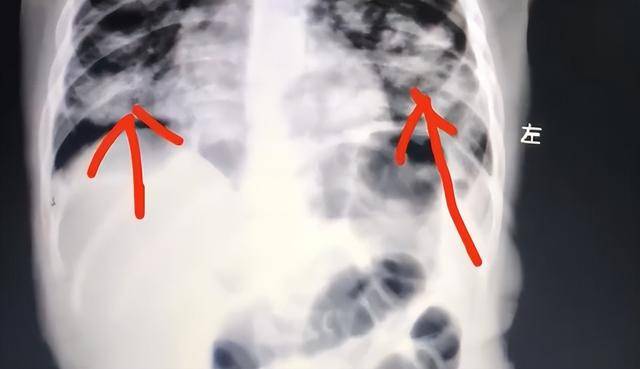

家长发现后,第一反应是立即用手抠孩子喉咙催吐,不料这一做法反而导致油脂被吸入肺部,引发严重吸入性肺炎。目前,孩子肺部已出现大面积感染变白。

油脂类物质一旦进入肺部,难以自行排出,会迅速引发炎症和感染,情况十分危险。